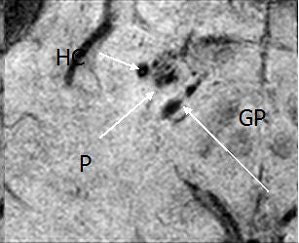

![]() |

| Above and below, susceptibility weighted imaging technique shows bleeding in the hippocampus (HC) and the adjacent putamen (P) and globus pallidus (GP), suggesting why the patient had short-term memory loss. Images courtesy of the department of radiology at Wayne State University. |